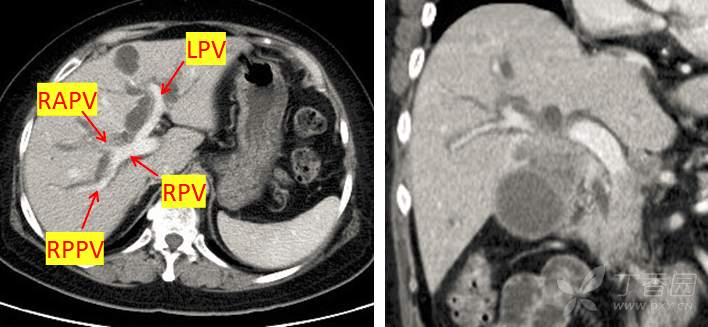

门静脉右前支间隙模糊,可疑受侵,图像如下:

肝静脉评估未见异常,如下图:

术前淋巴结评估如下: